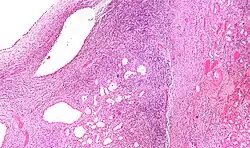

| Micrograph of a cystic nephroma (left of image). Normal kidney is seen on the right. H&E stain. | |

A cystic nephroma, also known as multilocular cystic nephroma, mixed epithelial stromal tumour (MEST) and renal epithelial stromal tumour (REST),[1] is a type of rare benign kidney tumour.

The characteristics of cystic nephromas are:

- Cysts lined by a simple epithelium with a hobnail morphology, i.e. the nuclei of the cyst lining epithelium bulges into the lumen of the cysts,

- Ovarian-like stroma that has a:

- Spindle cell morphology, and has a

- Basophilic cytoplasm.

Micrograph of a cystic nephroma. H&E stain.